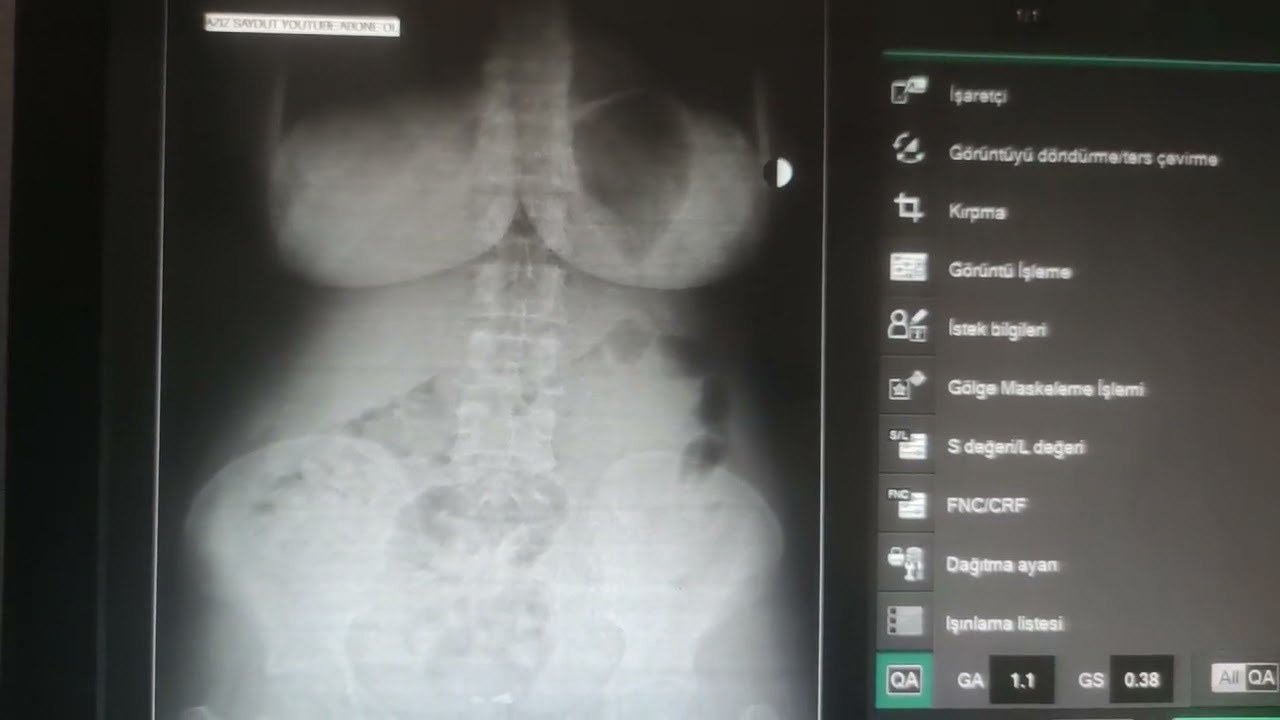

"Acil Serviste BT/Direkt Grafi Değerlendirme"

Dr. Öğr. Üyesi Ömer ÇANACIK

DEÜ Tıp Fak. Acil Tıp Anabilim Dalı